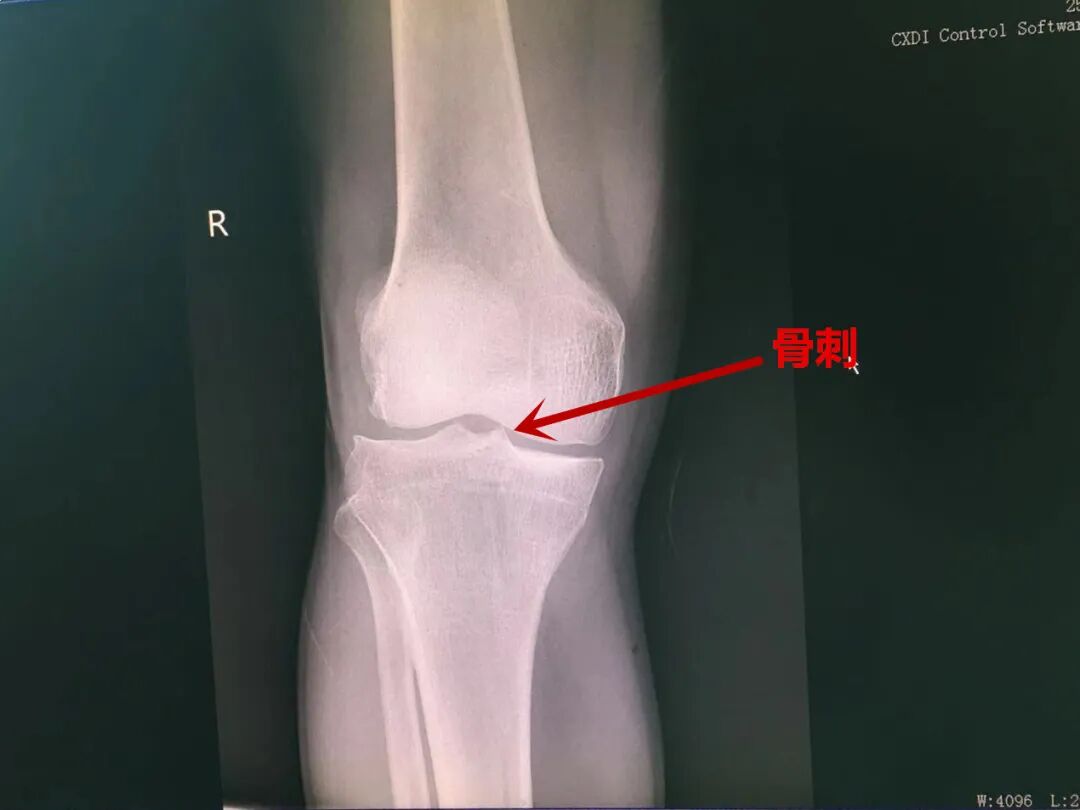

膝关节骨刺|痛痛痛 今年53岁的杨师傅经常从事半蹲位工作,素有膝关节疼痛,行走时疼痛明显,休息后能稍微好转。到新昌县中医院针灸科就诊检查后,何芳芳医生诊断为膝关节骨刺。经过一段时间的针刺、艾灸等治疗,杨师傅的膝关节病痛已经明显减轻了。 ● 什么是膝关节骨刺? “膝关节骨刺”又称为“膝关节骨质增生”,“膝关节骨性关节炎”,当关节软骨磨损到一定程度后,关节就出现了不稳定,骨骼会作出相应的反应,就会长出骨刺,用来增强关节稳定性,但是因增生的骨刺质地坚硬,表面粗糙,容易引发疼痛,从而影响正常的膝关节活动。 ● 如何保养和治疗呢? 针灸治疗膝骨性关节炎有比较好的效果,通过刺激膝关节周围穴位,调理气血,祛风寒、除湿、化瘀,可缓解疼痛,改善关节功能,阻止和延缓疾病的发展,保护关节功能。 ● 日常生活注意事项 1.避免过度剧烈运动,减少上下楼梯等运动;保持合适的体重,防止加重膝关节的负担,避免长时间下蹲,注意更换姿势。 2.局部热敷以改善局部循环,也可予外敷膏药,天气寒冷时应注意保暖,必要时带上护膝,防止膝关节受凉。 3.仰卧抬腿(股直肌锻炼):仰卧于床上,患腿上抬15度角左右,初做时可保持1~3分钟,练习一段时间后,争取达到10~15分钟。随后也可练习,随后也可练习用脚挑一个枕头,增加力量,每天2~3次。